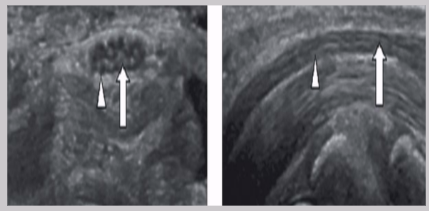

Normal US appearance of Achilles tendon

Common Achilles tendon pathology